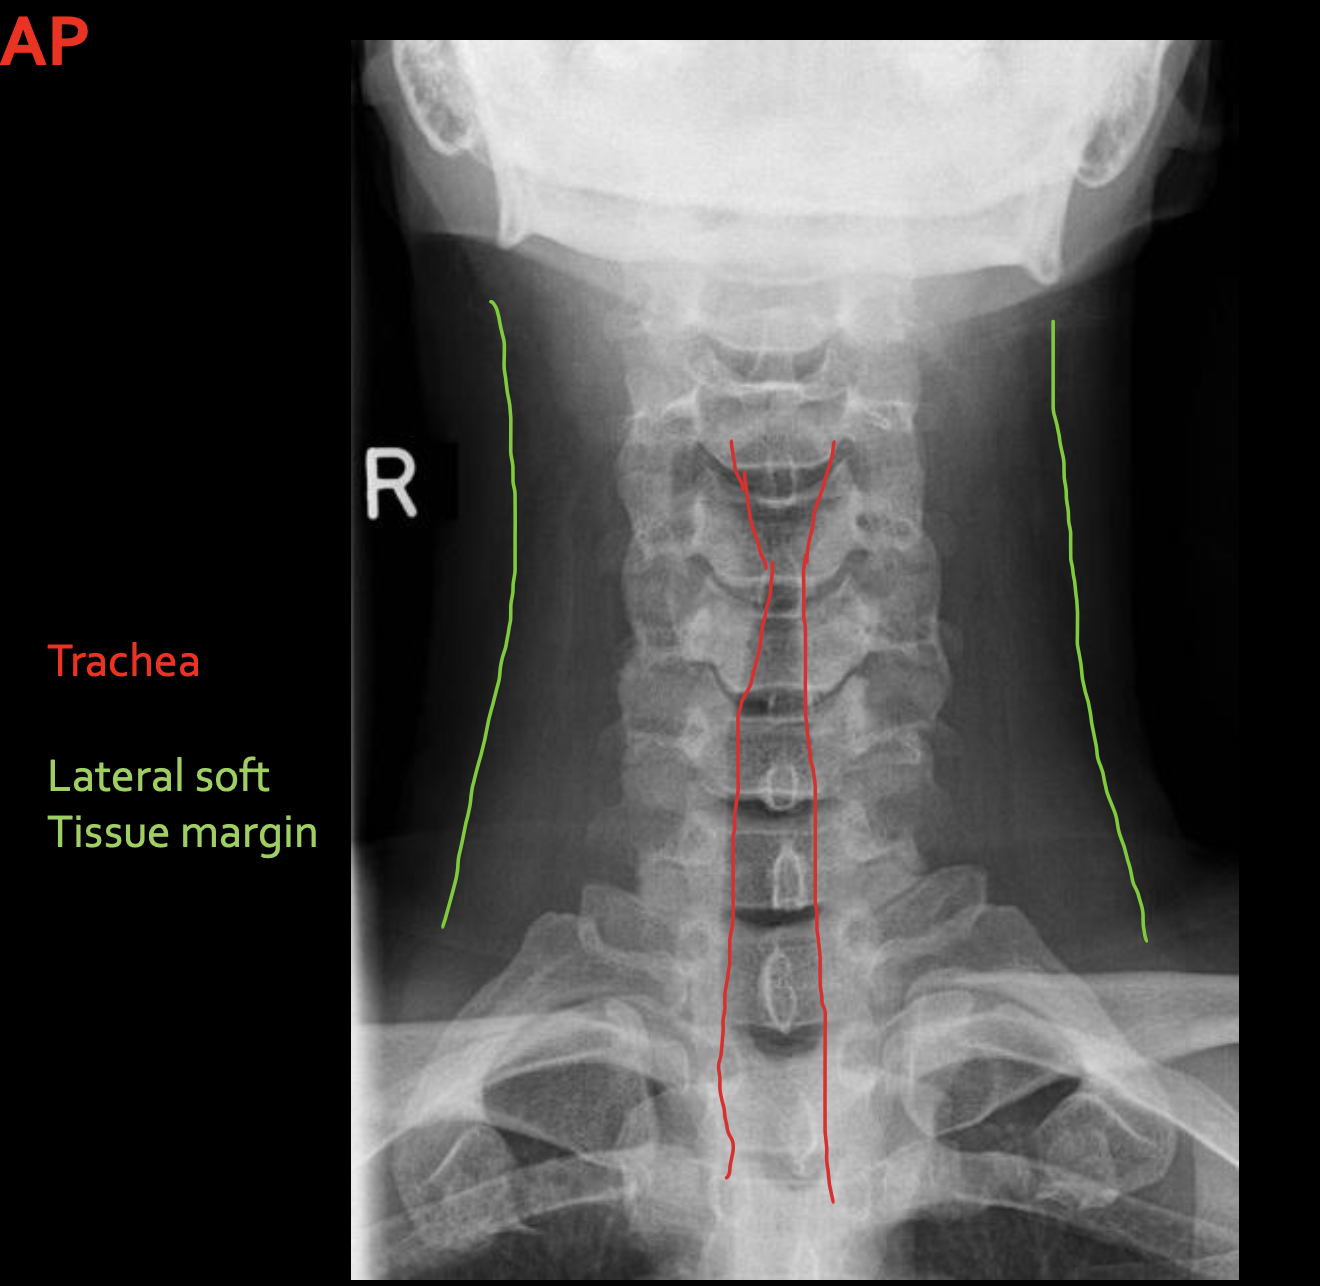

气管

Trachea